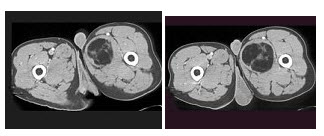

A.液体

B.脂类

C.空气

D.蛋白质

E.出血

51、单项选择题

根据所提供的图像,最可能的诊断是()

A.单纯囊肿

B.囊肿出血

C.肾细胞癌

D.腺瘤

E.以上都不是